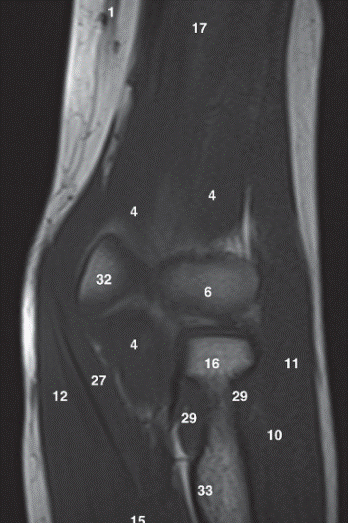

Label 1,4,6,16,32,33

1-Lt. Basilic vein

4=-Lt. Brachialis muscle

6-Capitulum of Lt. humerus

16=Head of Lt. radius

32-Trochlea of lt. humerus

33= Tuberosity of lt. radius

Label 6,16,17,18,22,25,32

6=Capitulum of lt. humerus

17=Lt. Humerus

18=Lateral condyle (lt. humerus)

22=Medial condyle (rt. humerus)

25=Olecranon fossa of lt. humerus

32=Trochlea of lt. humerus